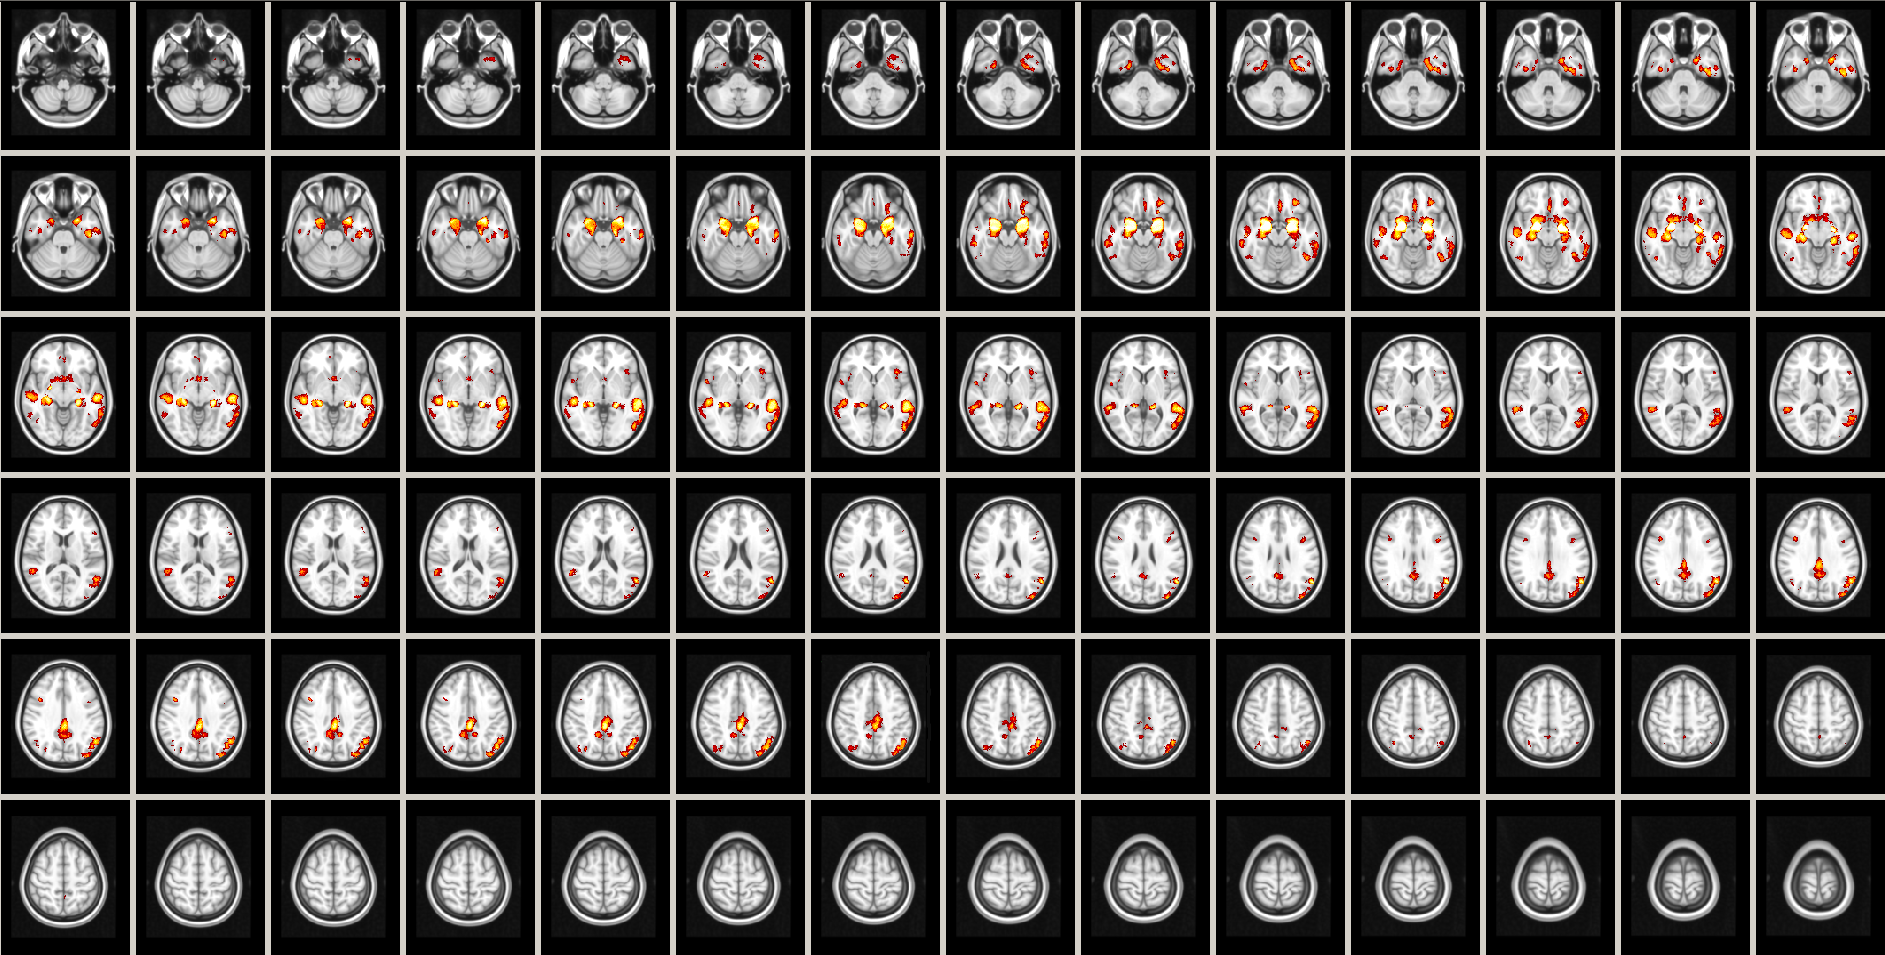

In a second experiment we fitted a polynomial and a Gaussian SVR and computed their F-test statistical maps to compare their behavior with the polynomial GLM. As an example, the map corresponding to the polynomial SVR is shown in Figure 1.

Refer to caption

Figure 1: F-test statistical map for the polynomial SVR, with significance level (α𝛼\alpha) filtering at 0.001, minimum cluster size of 100 voxels and transformed into Z-scores for improved visualization.